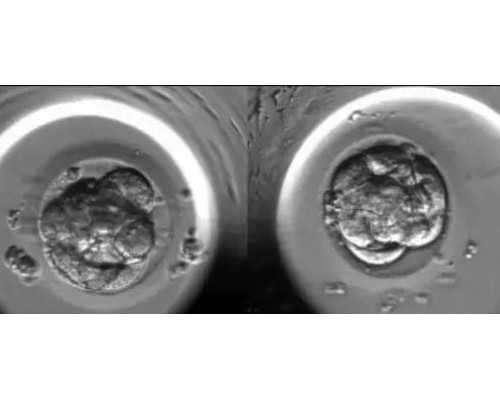

生殖医学专家提示,有不少男士在进入取精室后,由于心理紧张或环境改变而导致不能勃起或勃起后无法射精,这时要及时与医护人员沟通,可以先离开一会,稍作休息,调整心情之后再继续。如果最后还是自行取精,医生就会建议睾丸穿刺手术取精或者冷冻卵子。取精之后,实验室技术人员会对精液进行液化,活力筛选等处理,选出最优质的精子,然后把精子送去与卵子小姐汇合,小宝宝在不远处招手啦。